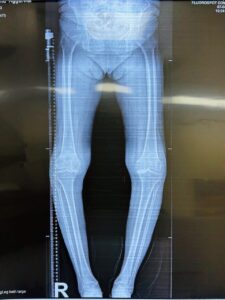

BEFORE SURGERY